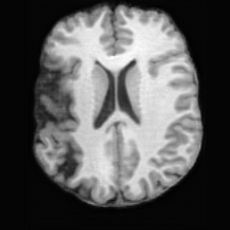

(a)PathologicalInput ImageSynthSR [18]Brain-ID [28]UNA [30]USBHealthyGround TruthRefer to captionRefer to captionRefer to captionRefer to captionRefer to captionRefer to captionRefer to captionRefer to captionRefer to captionRefer to captionRefer to captionRefer to captionRefer to captionRefer to captionRefer to captionRefer to captionRefer to captionRefer to captionRefer to captionRefer to captionRefer to captionRefer to captionRefer to captionRefer to caption(b)HealthyInput ImageConditionalLesion MaskUNA [30]USBRefer to captionRefer to captionRefer to captionRefer to captionRefer to captionRefer to captionRefer to captionRefer to captionRefer to captionRefer to captionRefer to captionRefer to captionRefer to captionRefer to captionRefer to captionRefer to caption

Figure 5: Comparison of bidirectional brain editing. (a) pathology-to-healthy, the circles and arrows highlight lesion regions and unsuccessful reconstructions; (b) healthy-to-pathology. Note that SynthSR and Brain-ID cannot perform healthy-to-pathology editing.

Pathology-to-Healthy Editing. Fig. 5 (a) presents comparison results on four input brain images with lesions of varying sizes, shapes, and densities. All competing models, although specialized for healthy brain image synthesis, struggle to reconstruct pathological regions, especially near lesion boundaries. In contrast, USB accurately reconstructs the corresponding healthy brain, even in challenging cases with large, high-density lesions where normal brain structures are almost completely obscured (last row). Tab. 2 provides a quantitative comparison for pathology-to-healthy editing, where USB achieves the best performance across all three datasets, demonstrating the effectiveness of its unified framework in reconstructing healthy brains from pathological inputs. Additional results are in Suppl. B.